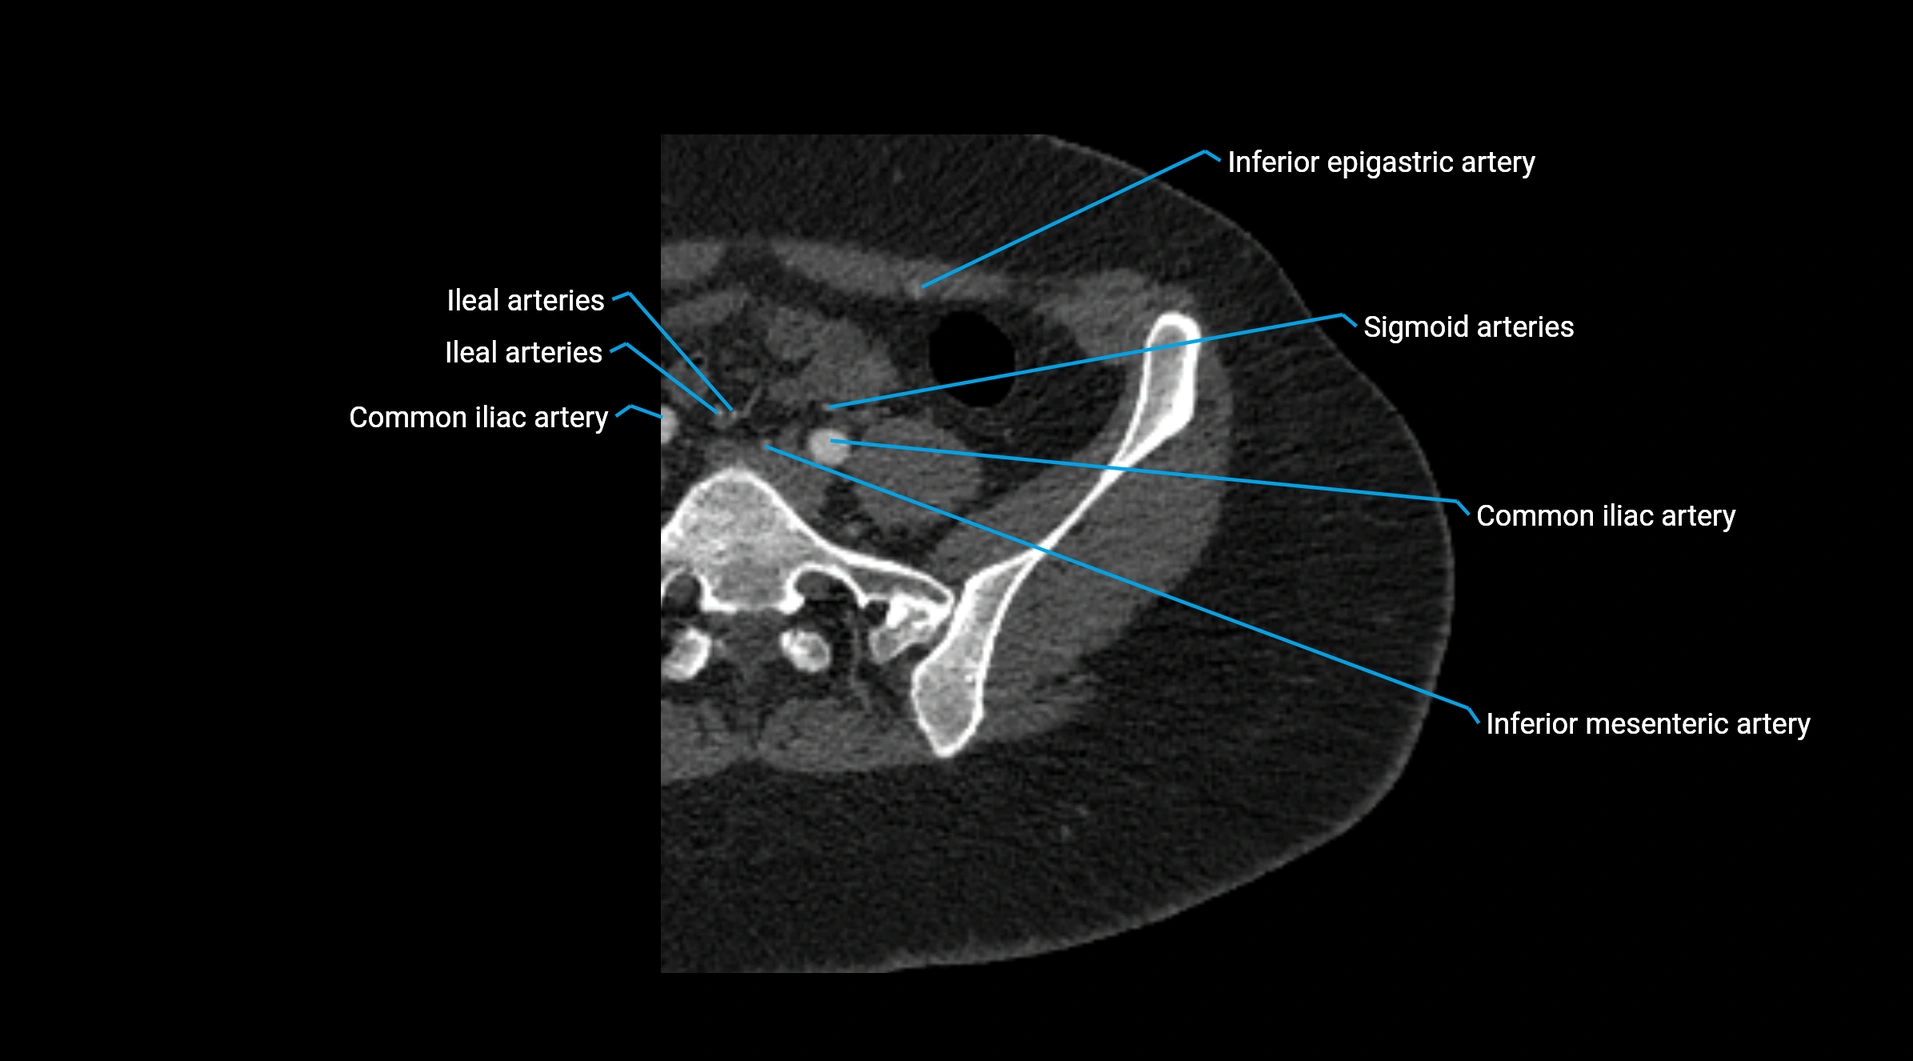

CT images

image

Contrast-enhanced CT (CTA):

• Gold standard for abdominal aortic imaging

• Provides excellent detail of lumen, wall, aneurysm, thrombus, and branch vessels

• Multiplanar and 3D reconstructions help in aneurysm measurement, stent graft planning, and dissection evaluation

• Unpaired visceral branches: celiac trunk, superior mesenteric artery (SMA), inferior mesenteric artery (IMA)

• Terminal branches: right and left common iliac arteries